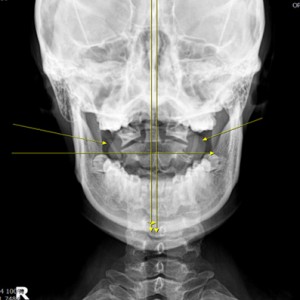

Catch Point 01. 안면비대칭

X·Y·Z축을 바로 잡는 안면비대칭 3D 입체교정

미간, 콧대, 턱, 목선 맞추기

눈썹 높이 수평

입꼬리 수평

두상 위치 균형

어깨 비대칭 개선

안면 두개골 엑스레이 검사

Submento Vertex View 포함

안면 균형검사

턱의 다양한 각도 사진 촬영